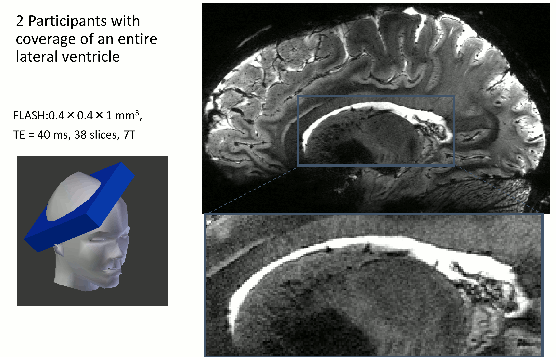

5.) CSF-volume redistribution

The T1-sensitivity in VASO makes it not only sensitive to changes in CBV, but it is actually also believed to be sensitive to volume redistribution of any other T1-compartments too. As such, Piechnik at al., Seong-Gi Kim, the Constable group and Manus Donahue proposed that there might be dynamic change of CSF that can contaminate the VASO contrast. In SS-SI VASO this effect can be accounted for with a balanced combination of TRs and flip angles, as such that CSF and GM have the same baseline signal. In this sequence setup, the VASO signal reflects both: (a) the CBV increase that is compensated with extravascular parenchymal CBV and (b) the CBV increase that is compensated with CSF volume decrease.

With this in mind, it shows an additional channel of potential VASO signal increase (negative VASO voxels): CSF volume reduction that are accompanied the GM volume increase.

Across multiple examples of strong tasks, I never found clear evidence for this to happen. A few examples are shown here. The only exception are global tasks, such as respiration challenges.